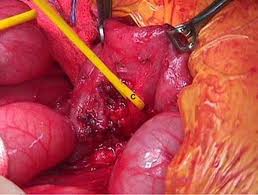

- Cirugía. El médico hace un corte en el abdomen y observará el páncreas y los tejidos que lo rodean para detectar la presencia de cáncer. Si existe un cáncer y no parece haberse propagado a otros tejidos, el médico puede extirpar el tumor.

- Cirugía. Puede emplearse cirugía para extraer el tumor. El médico puede extraer el cáncer por medio de alguna de las siguientes operaciones:

- Operación de Whipple, durante la cual se extrae la cabeza del páncreas, parte del intestino delgado y algunos de los tejidos que lo rodean. Se deja una porción suficiente del páncreas para que el órgano continúe produciendo jugos digestivos e insulina.

- Pancreatectomía total, mediante la que se extrae todo el páncreas, parte del intestino delgado, parte del estómago, el conducto biliar, la vesícula biliar, el bazo y la mayoría de los ganglios linfáticos de la región.

- Pancreatectomía distal, en la cual se extrae el cuerpo y la cola del páncreas. Si el cáncer se ha diseminado y no puede ser extraído, el médico puede operar con el fin de aliviar síntomas.